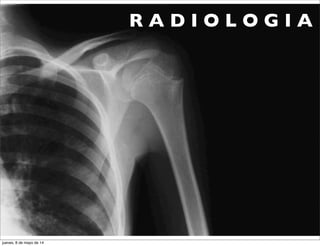

R A D I O L O G I A

•RX SIMPLE

•APROXIMACION DIAGNOSTICA

•EVALUACION DEL DAÑO ESTRUCTURAL

•MEDICION DE LA SEVERIDADY PROGRESION

•ESTABLECIMIENTO DE EFECTOS DEL

TRATAMIENTOY MEDIDA OBJETIVA DEL

COMPROMISO ARTICULAS